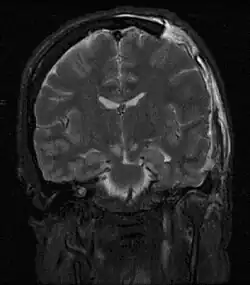

| Severely high ICP can cause the brain to herniate. | |

Severely raised ICP, if caused by a unilateral space-occupying lesion (e.g. a hematoma) can result in midline shift, a dangerous sequela in which the brain moves toward one side as the result of massive swelling in a cerebral hemisphere. Midline shift can compress the ventricles and lead to hydrocephalus.[21]